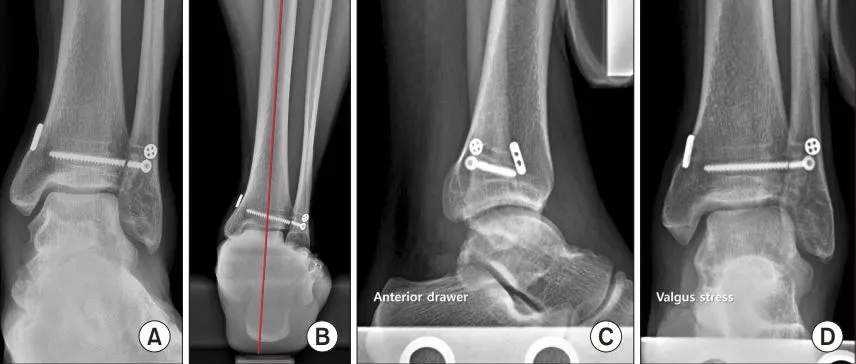

그림. 최종 추적 관찰 시 엑스레이 소견.

최종 추적 관찰에서 체중 부하 상태에서 찍은 발목 전후방 엑스레이(A)에서는 수술 전과 비슷하게 거골이 3º 외반으로 기울어진 상태가 계속 관찰되었습니다. 하지만 후족부 정렬은 수술 전보다 외반 변위가 줄어들며 개선된 모습을 보였습니다(B). 전방 견인 엑스레이(C)에서는 수술 전보다 거골의 앞쪽 이동이 2mm 줄어든 개선이 있었고, 외반 스트레스 엑스레이(D)에서는 외반 불안정성이 크게 호전되어 거골 기울기가 거의 없는 안정된 상태를 보였습니다.